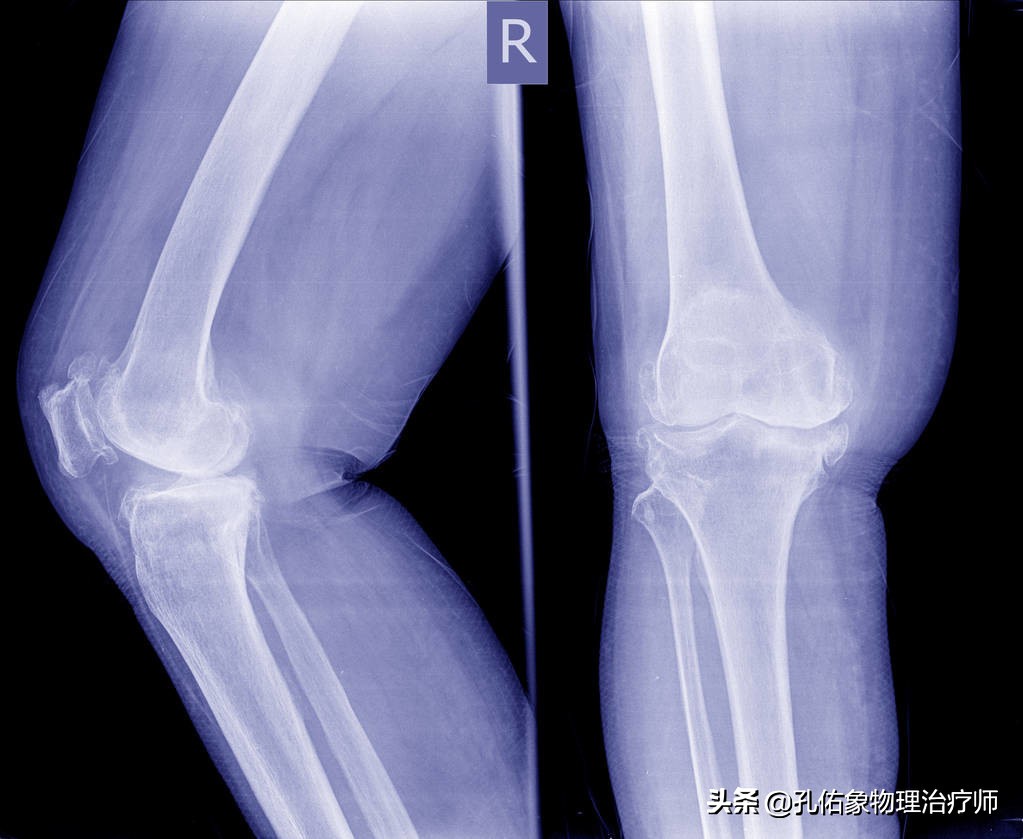

是导致老年人出现下肢无力、疼痛、走不远的最常见原因之一,主要的病理基础是我们关节内的软骨退变。

在我们正常的膝关节内,骨头表面有一层软骨,可以帮助您灵活的屈伸膝关节,可以帮助您承受压力负荷;若是因为体重负荷大、过度劳累等原因发生了磨损退变,会随着时间的推移,逐渐越来越严重,最终发生关节软骨的脱落,失去膝关节稳定后,会形成骨赘,也就是我们常说的骨刺或骨质增生。如下图所示:

当您出现膝关节退变,关节内到处都是骨刺时,您的关节活动开始困难,没法上下楼梯、下蹲、跑步,甚至严重时,哪怕走平路都不能。